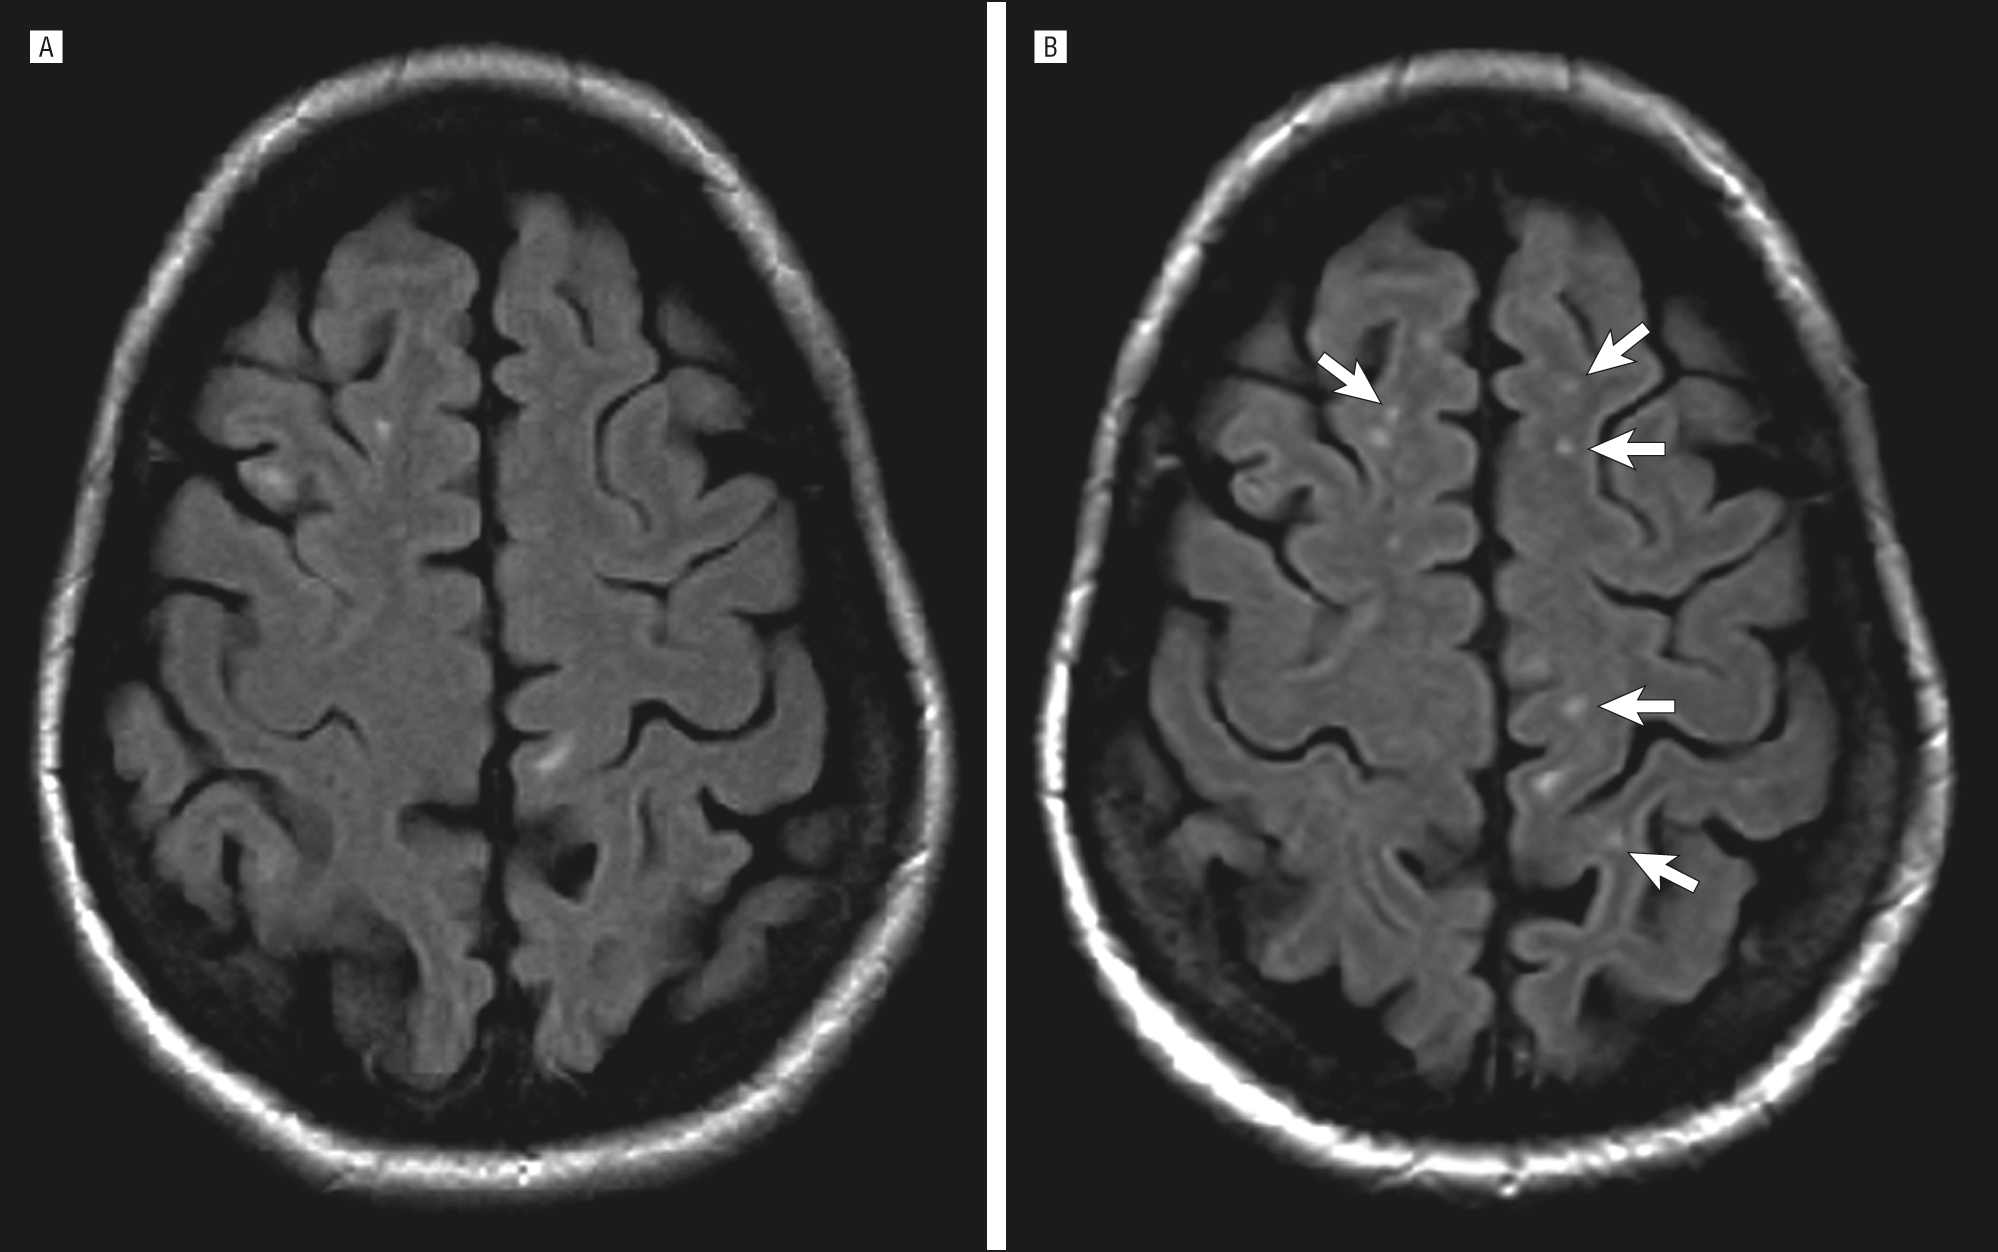

Иллюстрации и пояснения: гиподенсивный очаг на КТ головного мозга